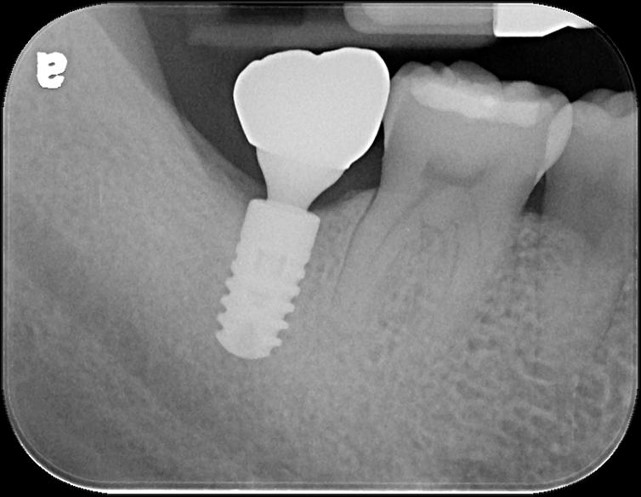

螺絲固定型假牙

治療後,咬合牙周適應良好

治療後,密合度良好